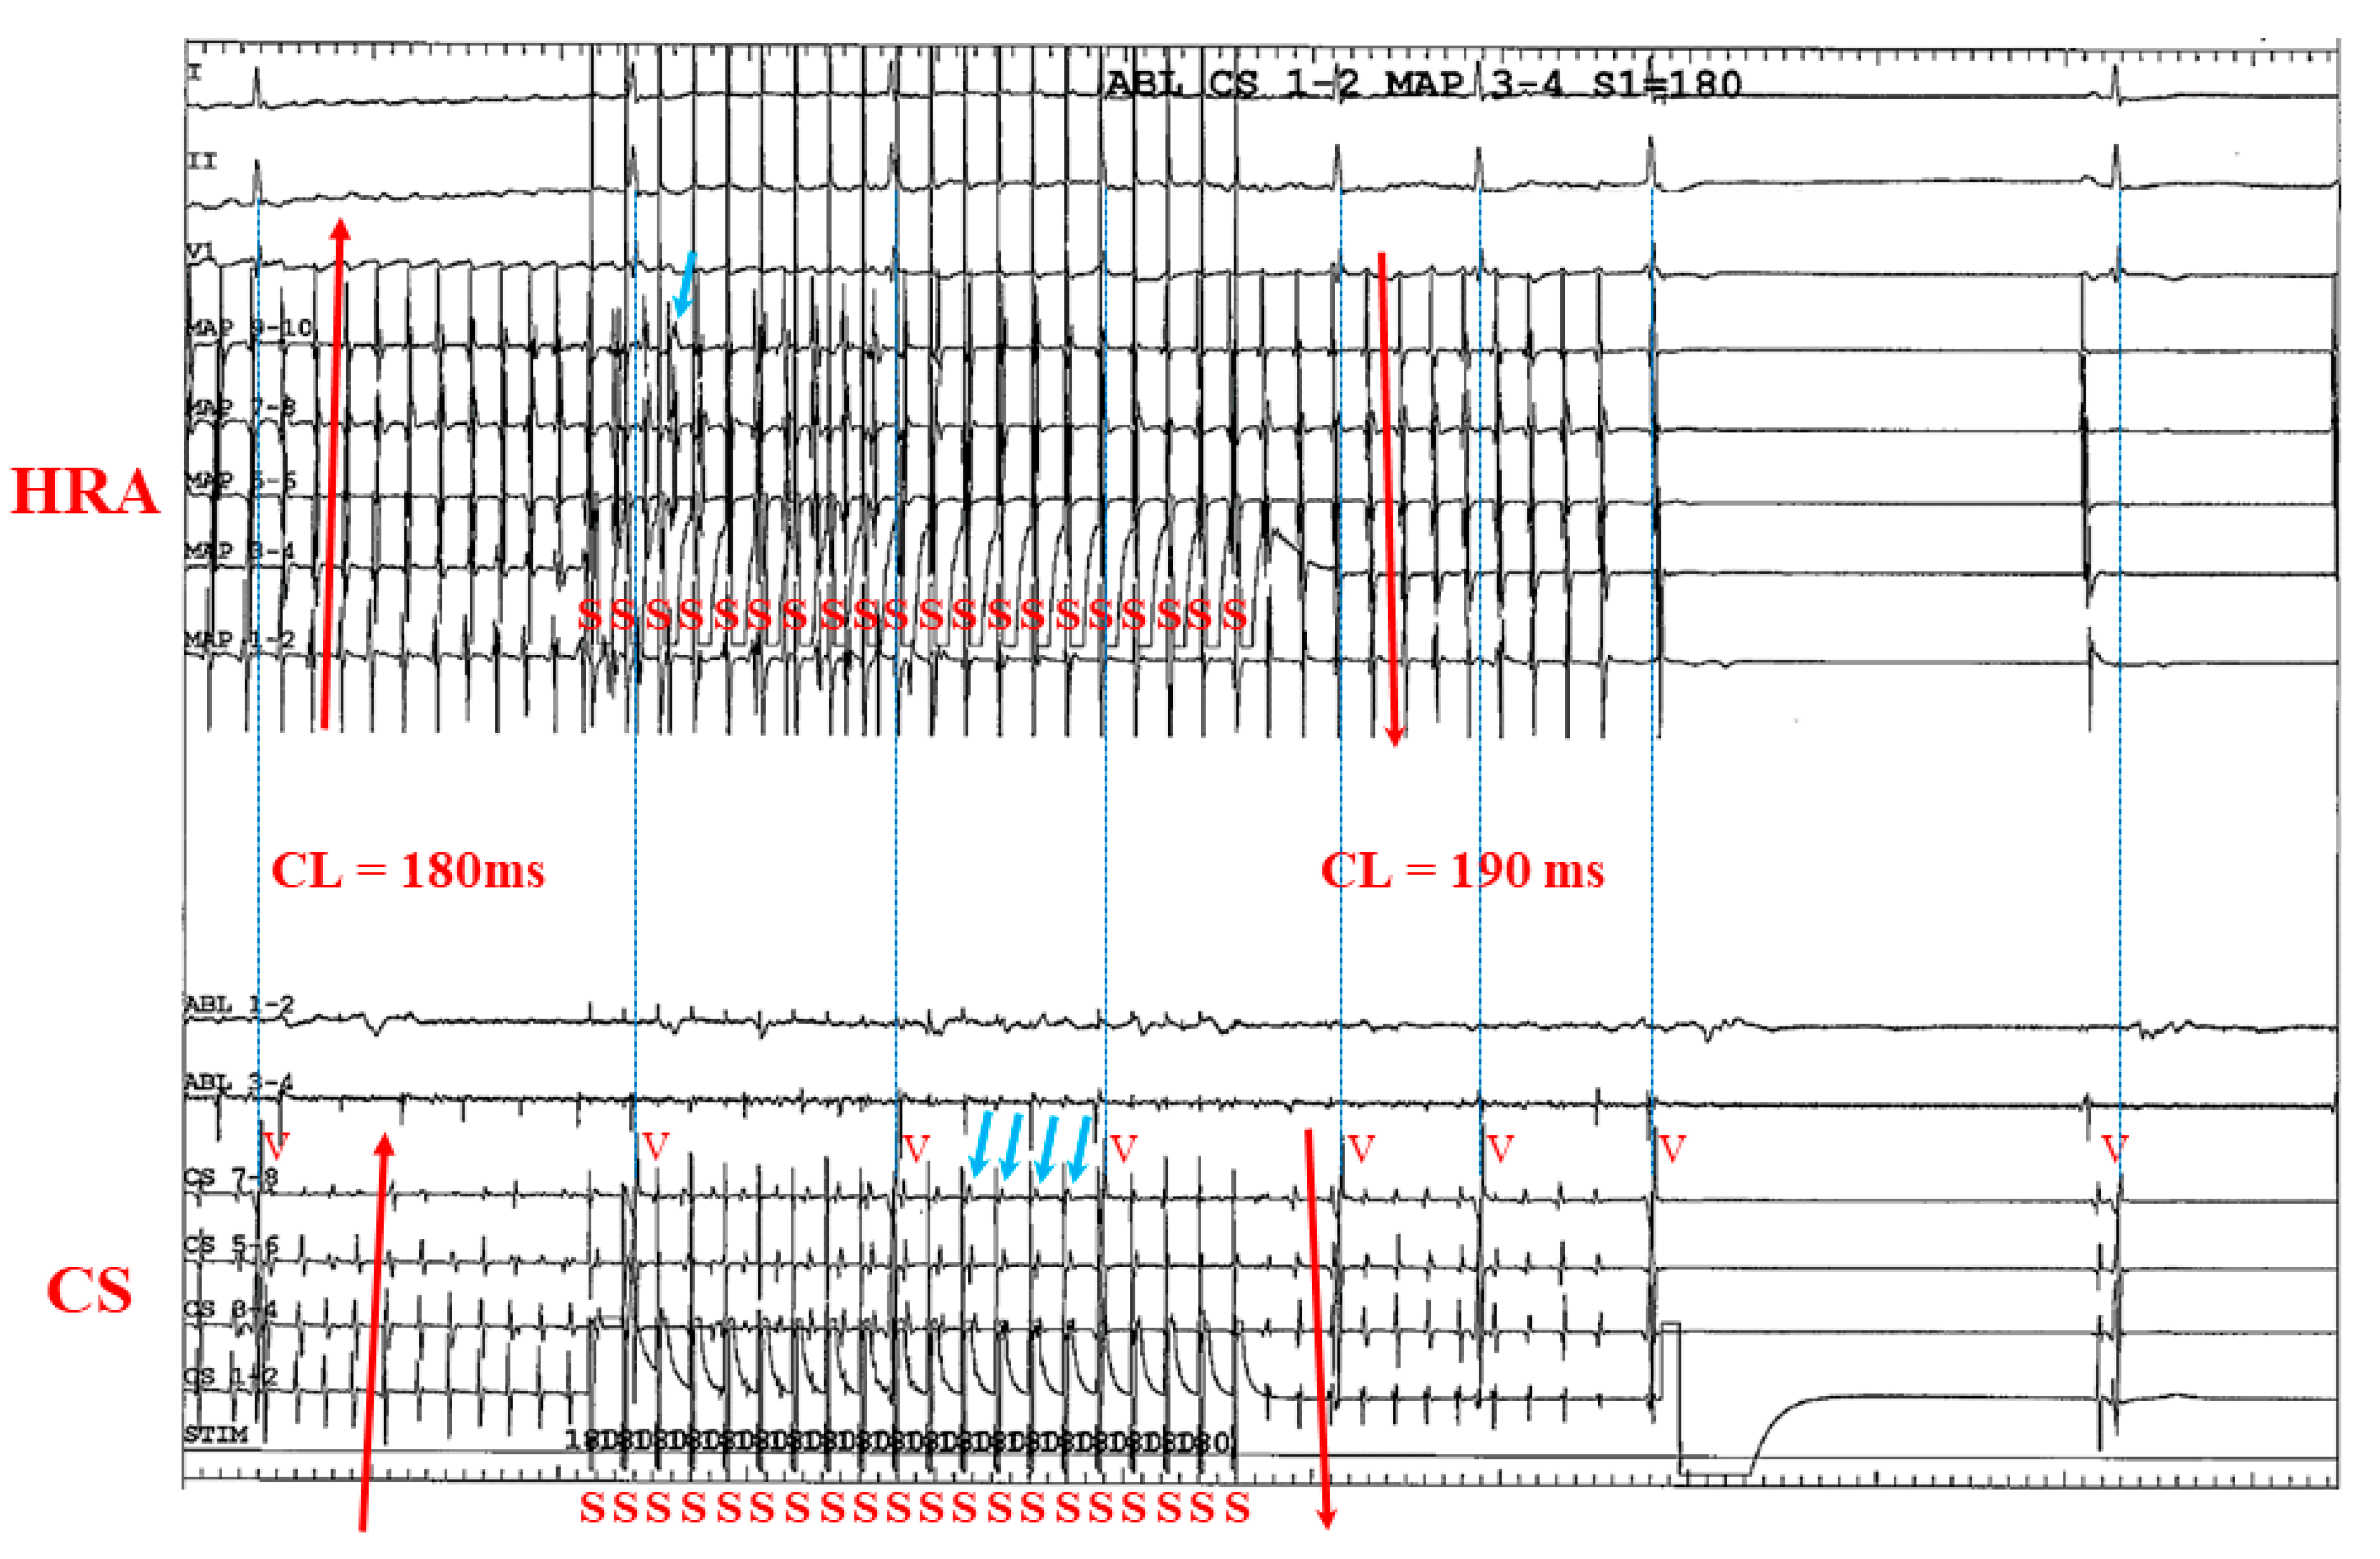

3.2. Representative Cases

3.2.1. Case 1: 42-Year-Old Man with Symptomatic PAF

3.2.2. Case 2: 72-Year-Old Man with Symptomatic PAF

3.2.3. Case 3: 67-Year-Old Man with Symptomatic PAF